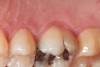

Figure 4   Indentations on tongue caused by forceful pressing of tongue on lingual surfaces. By pushing the tongue anteriorly, the airway is opened.

Figure 4

Bruxism and airway appear to be related to the patient’s attempt to develop a patent airway during a desaturation episode. The majority of SB episodes occurs in a supine position and may be associated with either a reduction in the airway passage or increase in its resistance. During resumption of ventilation following apnea, a co-activation of both jaw-opening and jaw-closing muscles produce dilation of the upper airway. This permits a rise in inspiratory flow and reduces upper airway resistance.37 It has been reported that 99% of all rhythmic masticatory muscle activities were associated with a change in the respiratory amplitude and frequency.19 Changes in lateral tongue contours, long associated with nocturnal bruxers, can now be explained. The patient attempts to provide a patent airway by activating the tongue muscles and forcing the tongue off the airway and against the teeth (Figure 4).